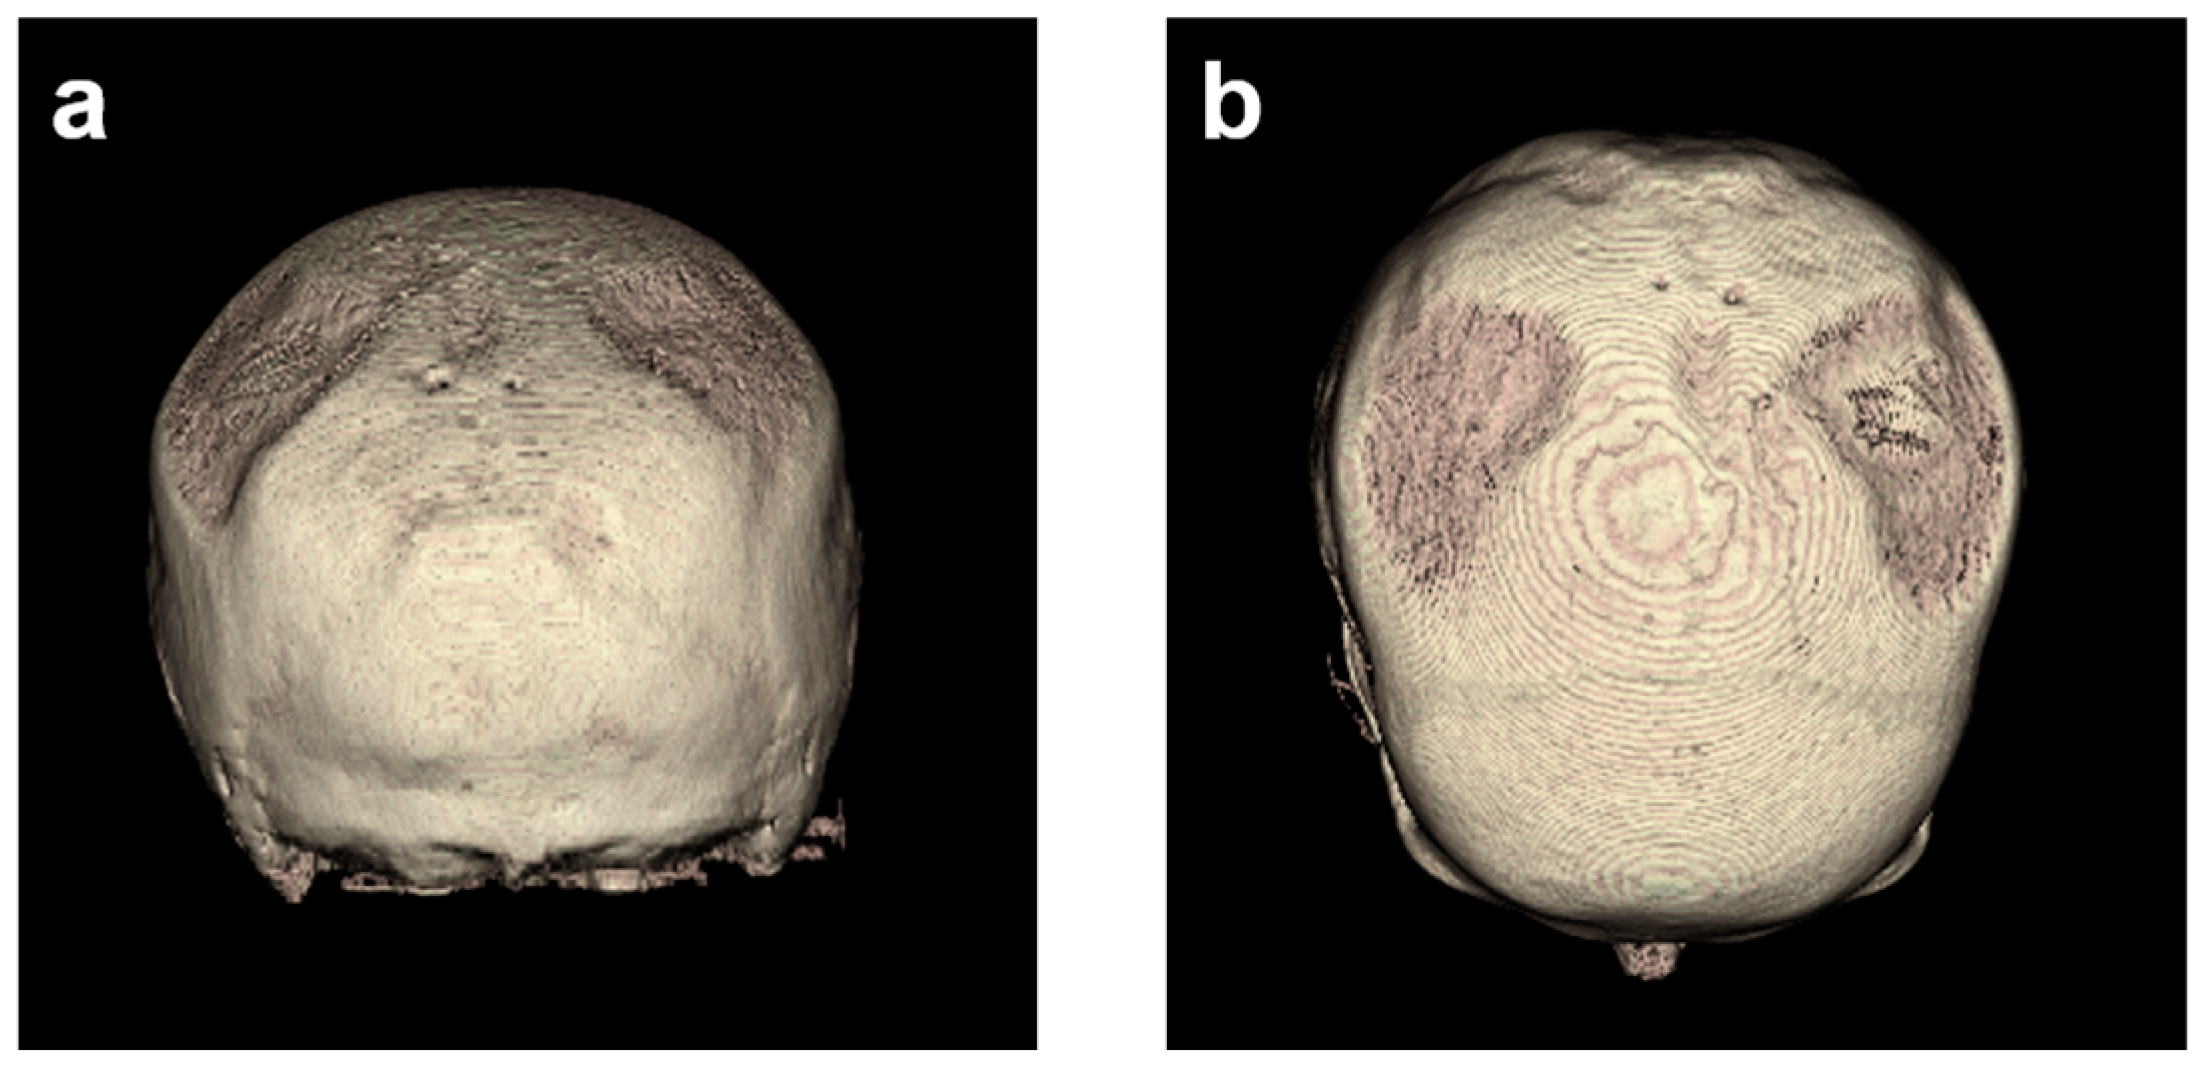

3.2. Descriptive Imaging Reports before and after 3D Reconstruction

3.3. Two-Dimensional (2D) Measurements of Biparietal Thinning

3.5. Comparisons of Changes in Bone Loss over Time